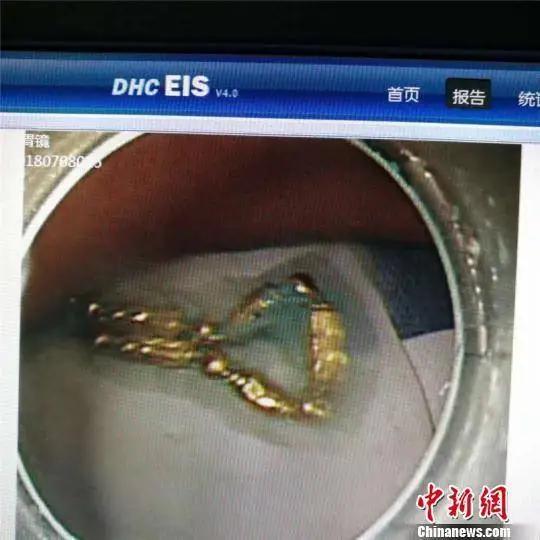

“菊花”失守72小时:一根网红“快乐棒”如何捅穿整条防线? 1️⃣ 急诊室凌晨3点的“社死”现场 值班护士小赵回忆:男子阿峰(化名)被推进来时,屁股垫着一次性护理垫,血渍外渗成一朵“玫瑰”。CT片上,一根20cm长、直径3cm的硅胶棒已戳破直肠,游离在腹腔——像一把倒插的“达摩克利斯之剑”。医生一句“怎么不早来?”让阿峰当场泪崩:“我以为是痔疮,忍忍就过了。” 2️⃣ 72小时“自救”全记录 • 第1天:异物塞入,肛门剧痛,他上网搜“如何自己抠出来”,结果只抠出更多血。 • 第2天:发烧38.5℃,灌肠、开塞露、筷子、镊子齐上阵,异物越捅越深。 • 第3天:肚子鼓成篮球,才想起打车去医院,却因“太尴尬”中途折返两次。 医生摇头:“再晚6小时,感染性休克直接进ICU。” 3️⃣ 网红玩具的“暗面” 同款商品详情页赫然写着“医用级硅胶、可全身水洗”,却找不到任何医疗器械备案号。评论区清一色“刺激”“秒到嗨点”,唯独缺一句“使用不当可能肠穿孔”。 更魔幻的是,客服自动回复:“亲,建议搭配润滑油哦~”至于润滑多少、深度几何?没人告诉你。 4️⃣ 医生给所有人的“菊花生存指南” ① 异物进入>5cm或无法自行排出,立即就医,别百度。 ② 任何“肛塞”玩具必须有底座或拉绳,防止“滑入失联”。 ③ 出现持续腹痛、发热、便血,就是穿孔前兆,挂急诊外科,别挂肛肠科排队。 ④ 带图问诊不丢人,丢人的是丢命。 5️⃣ 彩蛋:术后第5天,阿峰偷偷给护士站点了20杯奶茶 备注条写着:“替我谢谢医生,保住了我的‘第二张脸’。” 护士们把杯子排成一排,拍成“菊花守护联盟”打卡照。 评论区瞬间炸锅: “哥,你这一棒,捅开了多少人的羞耻盲区?” “奶茶我请,片子我绝对不看!” 留言区交给你: 如果朋友也遇到同款尴尬,你会陪他去医院,还是陪他继续“忍一忍”? 别害羞,评论区见真章!快乐自愈术 自制快乐法 快乐康复挑战